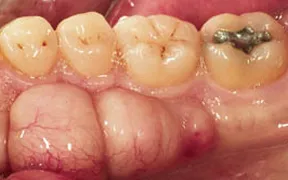

Periodontal Gallery Case 7

The large mass that you see above is simply an overgrowth of bone. It occurs in about 20% of the population. It only needs to be removed for cosmetic reasons, if it interferes with speech, or if a removal appliance such as a denture needs to be made.